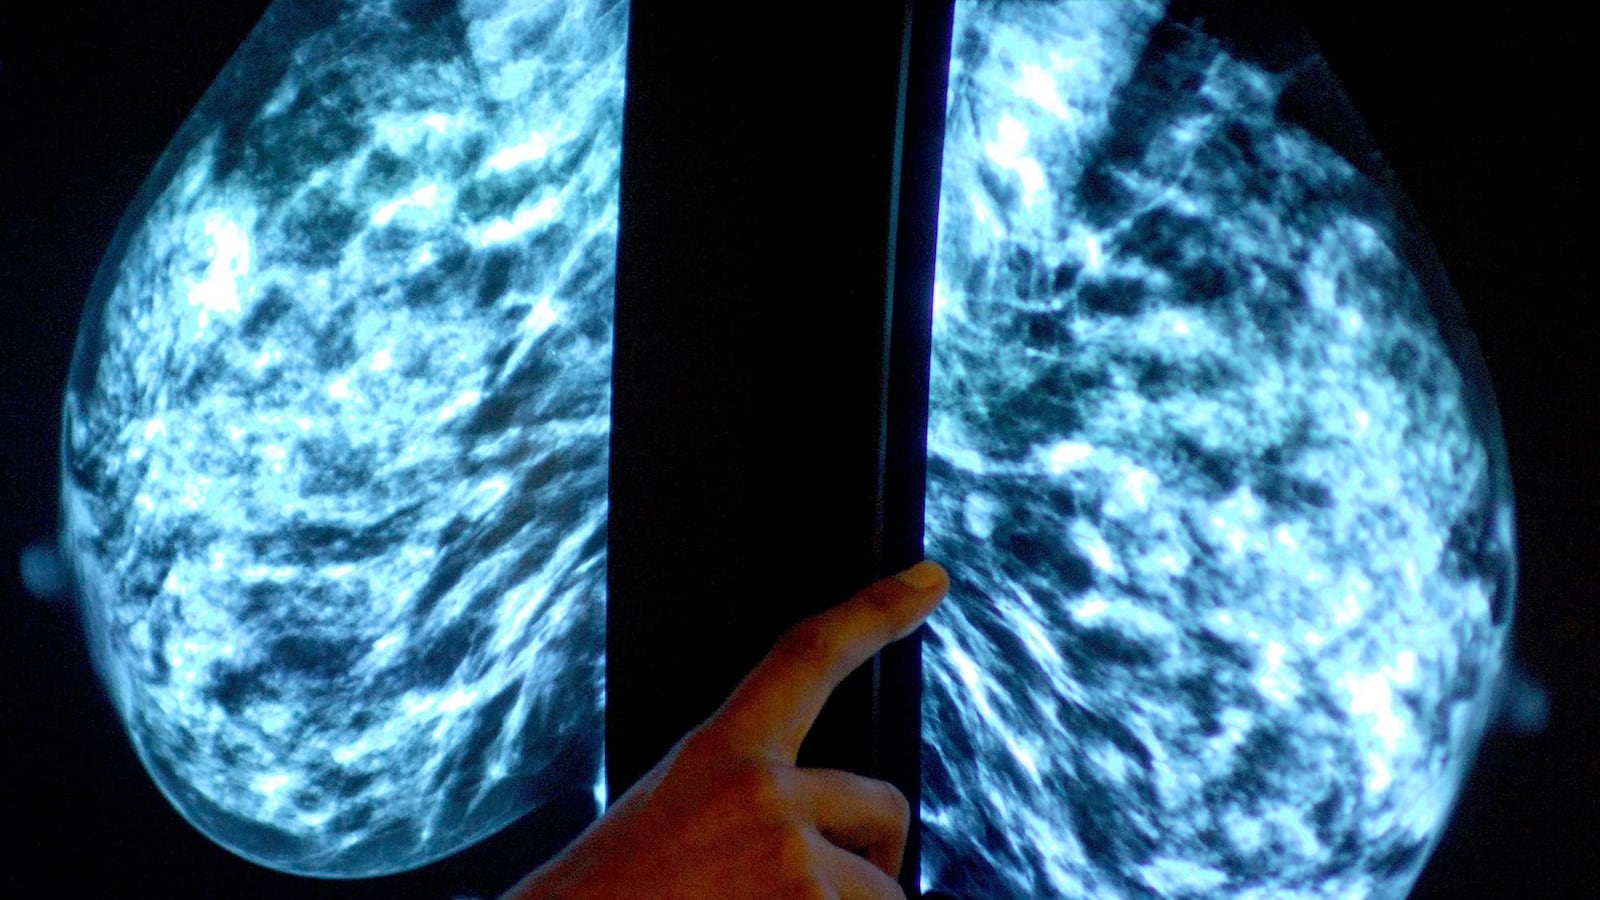

Concluding a massive international effort, scientists unveiled the discovery of pivotal signposts in DNA that may alert patients who are at high risk for breast, ovarian, or prostate cancer. The chief executive of the Cancer Research, U.K., whose non-profit funded the majority of the research, says it’s an important step on a long road to solving the genetic puzzle of cancer. While scientists have previously discovered “risk markers” for three other diseases, this new set of data doubles the list.